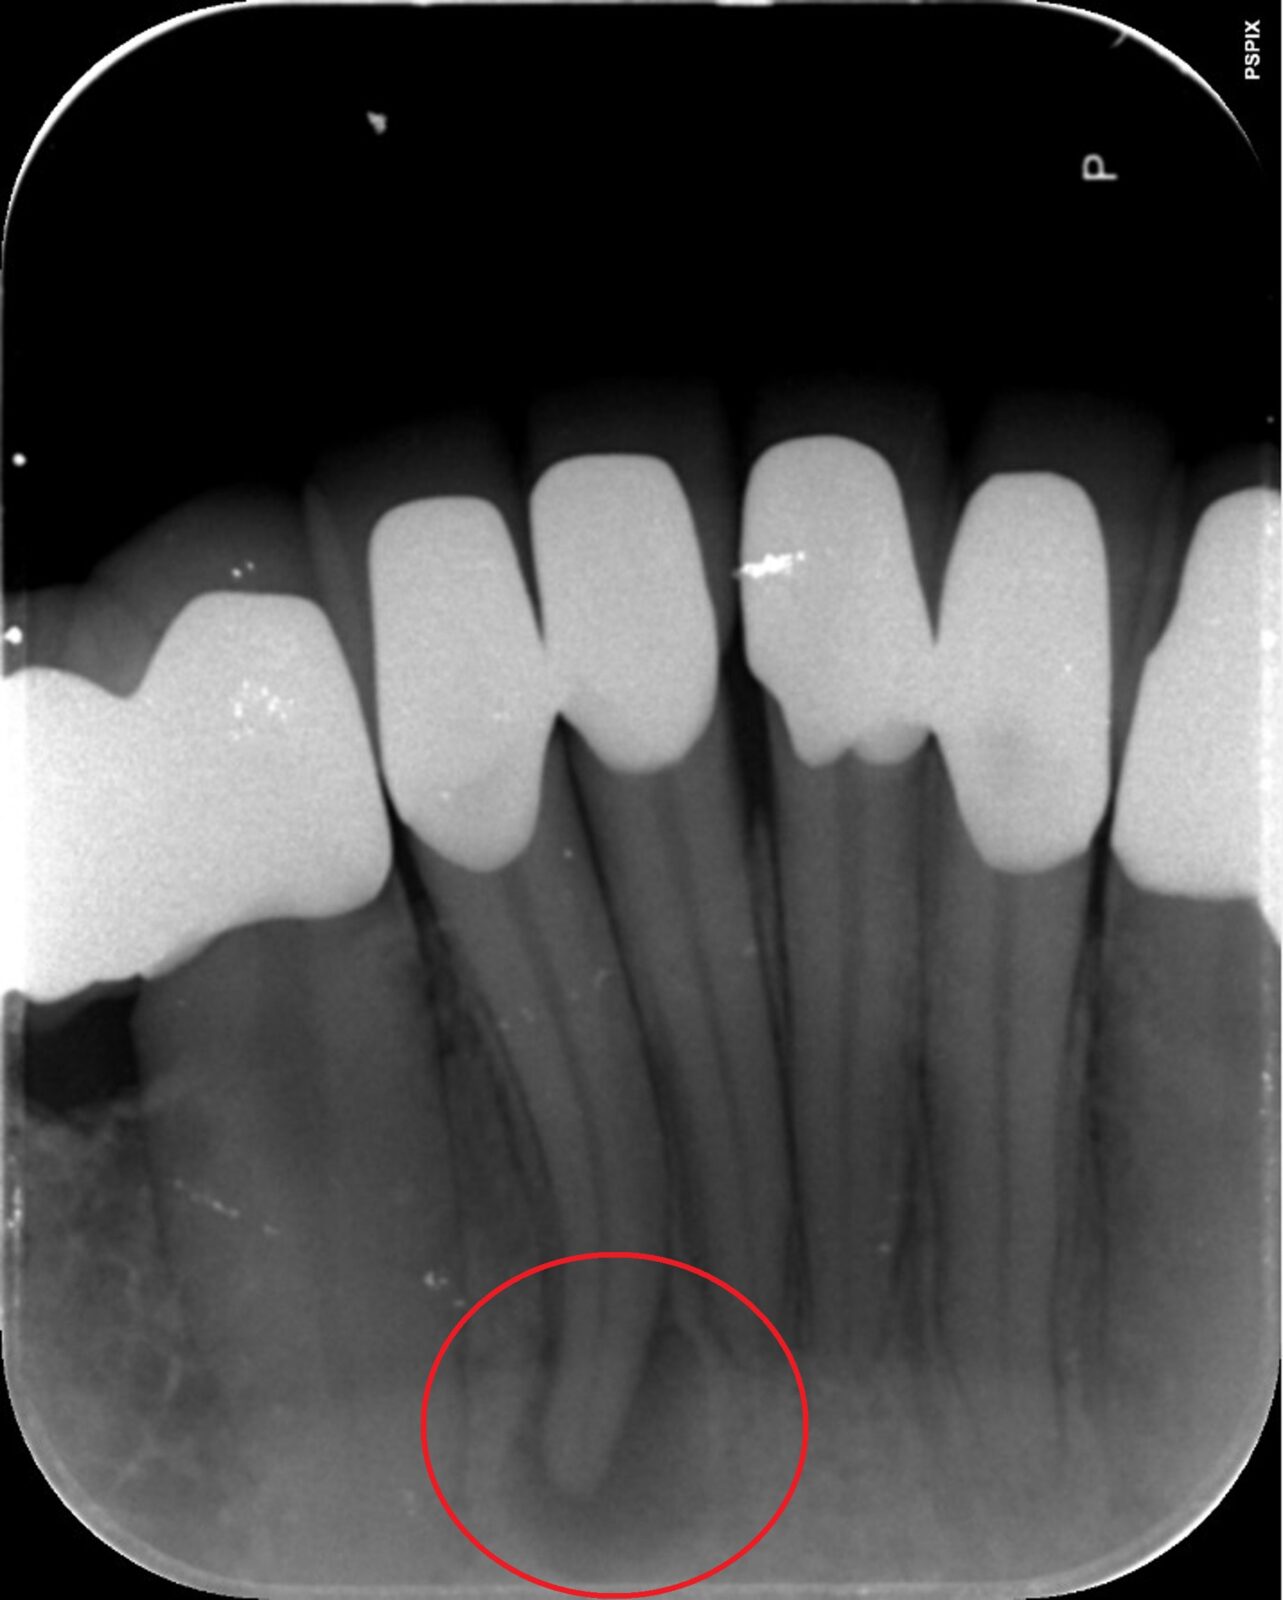

次の画像は、同じ患部をCTとレントゲンで撮影した画像です。

• 比較

「左」の写真がCTで、「右」の画像がレントゲンで撮影したものです。

赤丸で囲んだところには、黒い影が見えます。ここには炎症が起こっているのですが、右の写真には影がありません。つまり、2次元のレントゲンだけで診断した場合、問題のある部分は治療しない選択をするため、最終的には抜歯の運命をたどるケースです。